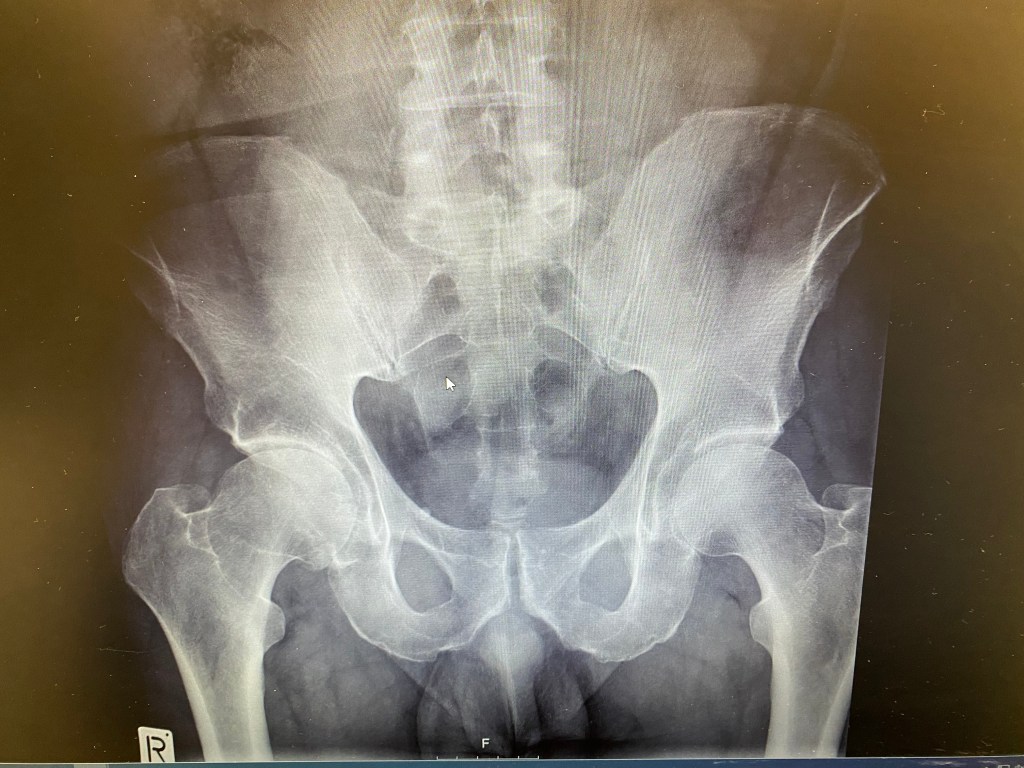

This Xray from several years ago shows the difference in spacing between the pelvic bone on the L and the R femoral head [top of thigh bone]